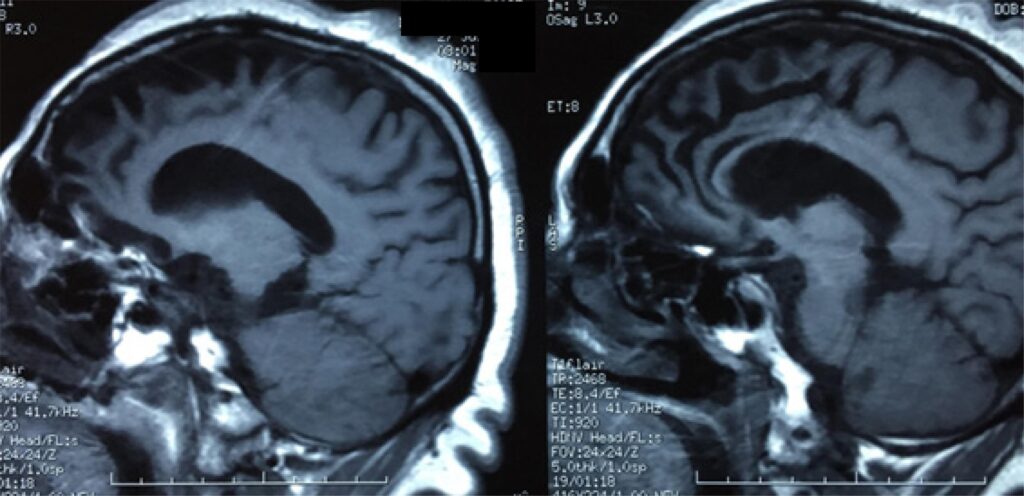

Lillo y Leyton (2016) reportan la presencia de cambios cerebrales a nivel micro y macro.

Entre los cambios macroscópicos se observa que hay una marcada atrofia en la regiones frontales y temporales, llegando a ser tan severa que los giros pierden un volumen importante. Estas pueden generar cicatrices y pérdidas de neuronas a nivel cortical y subcortical.

En la RM estructural se aprecia una atrofia en la corteza orbitofrontal, mesial e insular anterior y núcleos basales. A nivel funcional, una reducción selectiva en conexiones como el fascículo longitudinal superior, fascículo uncinado, cíngulo, cuerpo calloso y las conexiones que tienen con el lóbulo frontal.